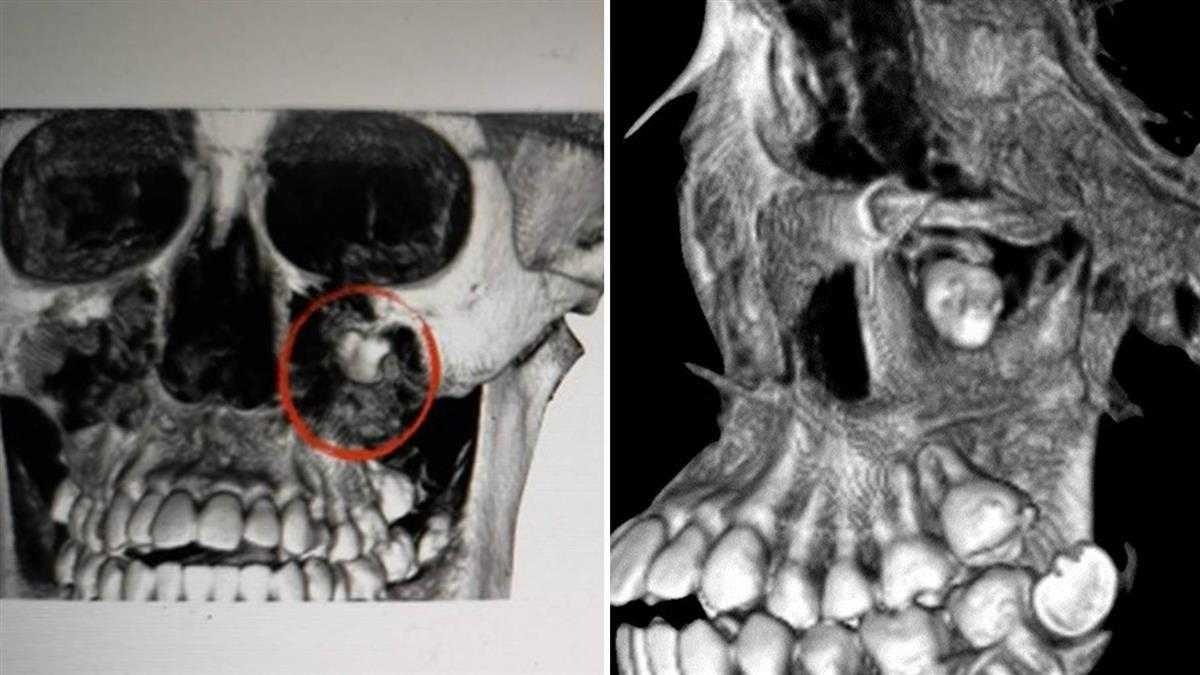

| Hình ảnh chiếc răng khôn mọc dưới hốc mắt. Ảnh: EBC. |

Sau khi chụp cắt lớp, bác sĩ phát hiện một chiếc răng khôn mọc dưới hốc mắt. Nó nằm trong một u nang dưới lớp da mặt, khi sưng lên chiếm toàn bộ diện tích má, các xoang trên mũi. Đây là nguyên nhân chính dẫn đến những đợt đau răng kéo dài của LuLu.